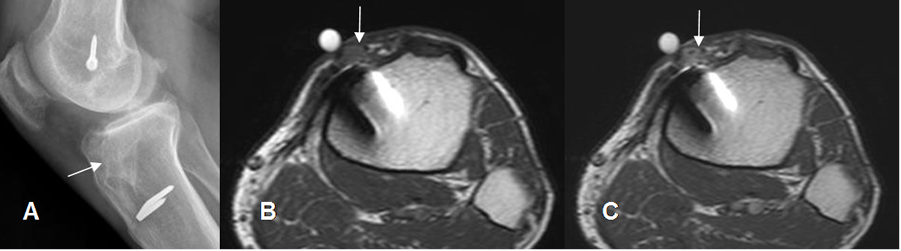

Fig 47 B. Osteomielitis asociada a Qx.

A: Rx lateral. PostQx por reconstrucción del LCA. Hay supuración intermitente en relación con el material de fijación y aumento de la densidad de la tibia, por osteomielitis crónica.

B: RM axial en T1 simple y C: RM axial en T1 con contraste. Marca en el orificio de supuración, encontrando cambios inflamatorios en los tejidos blandos que realzan con el contraste, en relación con la grapa metálica.